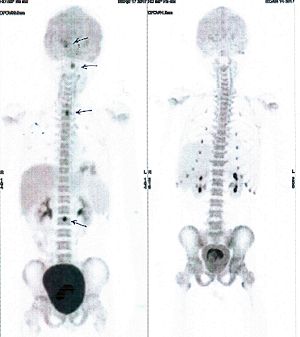

CASE NO: 16 (GLIOMA)

Teenage boy with glioma spreading to the spinal cords (arrows) and urinary retention. After a few treatment, all the cancer went into remission, and there is no more urinary retention.

CASE NO: 31 (LUNG CANCER WITH BRAIN METASTASES)

A 40+ woman with lung cancer and brain metastases failed all treatment including radiotherapy and chemotherapy. She cannot walk. After a few treatment, the left lung cancer is gone, and all the brain metastases are gone. She is starting to walk again. One set of pictures shows the left lung cancer, and the other set of pictures show the brain: on top is BEFORE TREATMENT, bottom is AFTER TREATMENT.